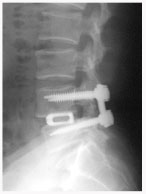

후외방 유합술(Posterlateral fusion) : 광범위한 후방 감압술 후 척추 외측에 있는 후관절과 횡돌기 간의 유합을 얻는 것.

- 충분한 감압을 얻을 수 있다.

- 신경 손상의 위험이 적다

후방 요추체간 유합술 (PLIF) : 광범위한 후방 감압술 후 추간판(디스크)을 제거한 후 골이식을 시행하여 추체간 유합을 얻는 것

- 후외방 유합술에 비해 절개가 적다

- 신경근에 대한 충분한 감압이 이루어진다

- 추간판(디스크)로 인한 동통 및 재발이 없다

- 추간판 높이를 정상으로 회복시켜 준다

- 척추 정렬을 정상으로 회복시켜 준다

* 현재에는 최소 침습적인 방법으로 적은 절개를 통해 가능하다